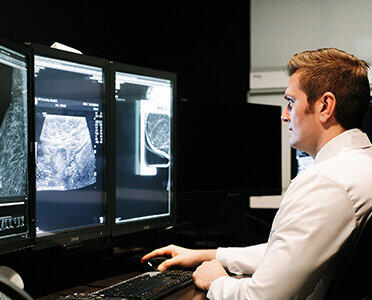

تشخیص دقیقتر سرطان با هوش مصنوعی مایکروسافت

شرکت مایکروسافت بهعنوان یکی از غولهای فناوری دنیا با کمک هوش مصنوعی، ابزاری برای تصاویر آنالیز دقیق تصاویر پزشکی ارائه کرده است. اهمیت تشخیص درست جزئیات تومور و سلولهای سرطانی در تشخیص این بیماری و یا درمانهای پیشرفته مانند ایمونوتراپی، اهمیت زیادی دارد.